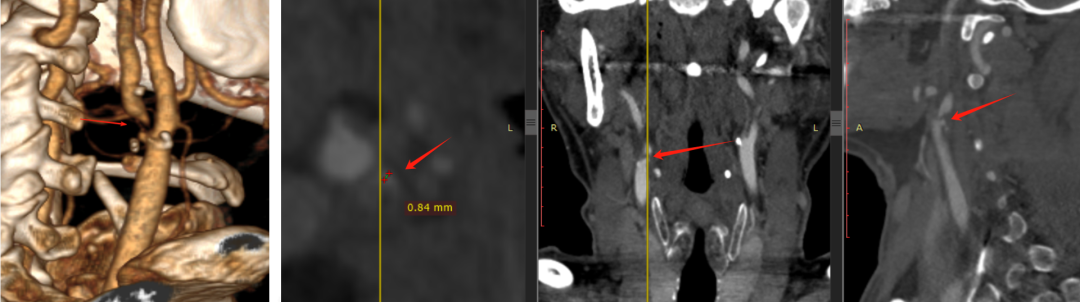

王盛教授分享了首都医科大学附属北京安贞医院的一例极具代表性的临床病例,并引导了现场专家对于颈动脉狭窄三种主流术式选择策略的深度探讨。患者为43岁男性,无症状,体检发现右侧颈动脉重度狭窄(70-80%),影像学(超声、CTA)提示为“次全闭塞”,病变长度约24mm。患者相对年轻且合并多种心血管高危因素,这使得术式选择充满了博弈,是选择经典的金标准CEA,还是微创的CAS,抑或新兴的TCAR?针对此病例,现场讨论嘉宾从解剖条件、全身状况、斑块性质三个维度进行了深入剖析。

波科支架怎么样波科@CEC2025|TCAR新技术手术交流会精彩荟萃_https://www.jmylbn.com_新闻资讯_第8张

波科支架怎么样波科@CEC2025|TCAR新技术手术交流会精彩荟萃_https://www.jmylbn.com_新闻资讯_第9张

1、解剖适应性

郭大乔教授、刘建林教授、吴巍巍教授一致认为,该患者颈总动脉直径、病变位置及血管入路条件非常适合进行TCAR。郭大乔教授补充道,若病变长且狭窄,可选择CEA。

2、术式比较

刘建林教授指出,若患者心肺功能良好,CEA同样是合理且有效的选择。陈忠教授提到,鉴于病变为“次全闭塞”,若行经股动脉的CAS,在通过病变放置保护伞时存在较高的栓塞风险。因此,决策天平在CEA与TCAR之间倾斜。

3、斑块稳定性评估

史伟浩教授强调,除了解剖学,斑块性质的评估至关重要。杨轶教授建议对高危患者采用高分辨率磁共振成像或超声造影来检测斑块内的新生血管、脂质核心和钙化情况,以判断其稳定性。郭大乔教授补充称,若通过超声造影可看到新生血管,判断为不稳定斑块,一般来说,CT值< 20 Hu,血栓或大的脂质坏死核心成份可能大,>40 Hu则纤维成份较多,>100 Hu则倾向于较稳定的斑块成份,钙化斑块的CT值会更高。针对该病例行TCAR较CEA更安全,因为TCAR逆流脱落血栓捕捉率高。

该病例对CAS、CEA与TCAR均无绝对禁忌。评估斑块稳定性时,高分辨率核磁或造影虽有参考价值,但临床表现,如术前有脑梗或TIA史,即可基本判定为不稳定斑块。本例病变属“次全闭塞”,经股动脉CAS在通过病变时存在碎屑脱落风险。就现有数据比较,TCAR的临床证据颇具优势,其围术期卒中发生率低于CAS,颅神经损伤率又低于CEA。因此在TCAR与CEA均适用时,优先选择TCAR;若无TCAR条件,CEA是合理替代,而CAS风险较高,可作为后续选择。总体而言,在传统优选CEA的基础上,如今TCAR提供了一个非常适宜的新选择。